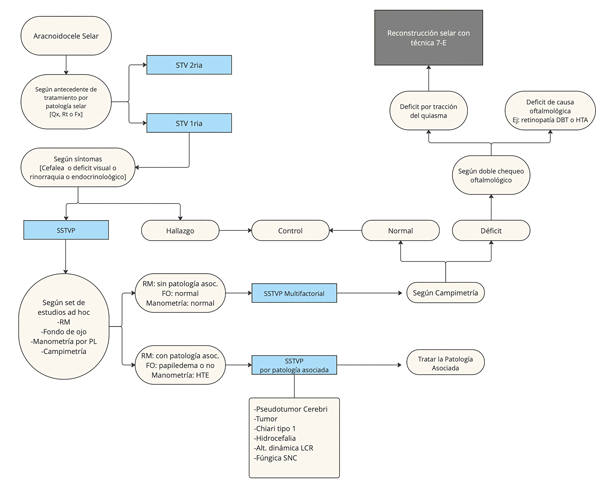

El único caso en el que progresó el déficit visual fue en una paciente que a su vez presentó panhipopituitarismo. Durante el seguimiento se reveló que tenía diagnóstico de histoplasmosis del sistema nervioso central. Interpretamos que cometimos un error en el manejo de la paciente, en virtud de un diagnóstico fallido. Esta paciente presentó una silla turca primaria asociada a un aumento de la presión intracraneana por la patología fúngica; por lo tanto debería haberse tratado la HTE y no debería haberse realizado la reconstrucción selar. Luego de este caso, agregamos a nuestro algoritmo de manejo la histoplasmosis (endémica en nuestra región) como causa de la silla turca primaria asociada al aumento de la presión intracraneana y el uso de manometría para descartar cualquier causa no identificada previamente, con lo cual nuestro algoritmo preliminar fue modificado.

Así también, en un caso sin mejoría, se objetivó una alteración en la dinámica de flujo de LCR sin llegar a constituir una hidrocefalia. Considerando que la alteración de dicho flujo puede generar cierto grado de HTE sin un cuadro florido de hidrocefalia, por lo que también decidimos agregar esto en el algoritmo (Figura 4).

Figura 4. Algoritmo final para la selección de pacientes candidatos a reconstrucción del piso selar por STVP. FO: fondo de ojo. HTE: Hipertensión endocraneana. PL: punción lumbar. RM: Resonancia magnética. SSTVP: Síndrome de silla turca vacía primaria. STV: Silla turca vacía.